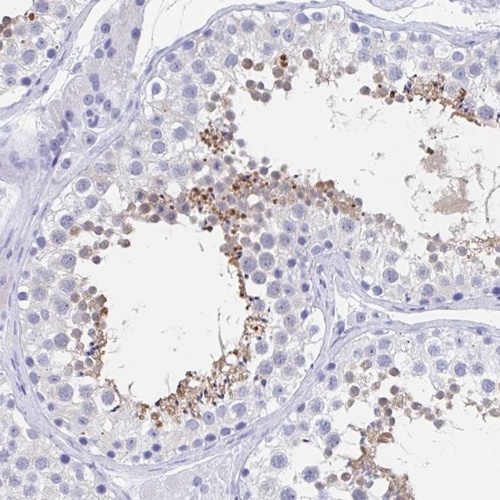

Immunohistochemistry analysis in human testis and pancreas tissues using Anti-C10orf53 antibody. Corresponding C10orf53 RNA-seq data are presented for the same tissues.